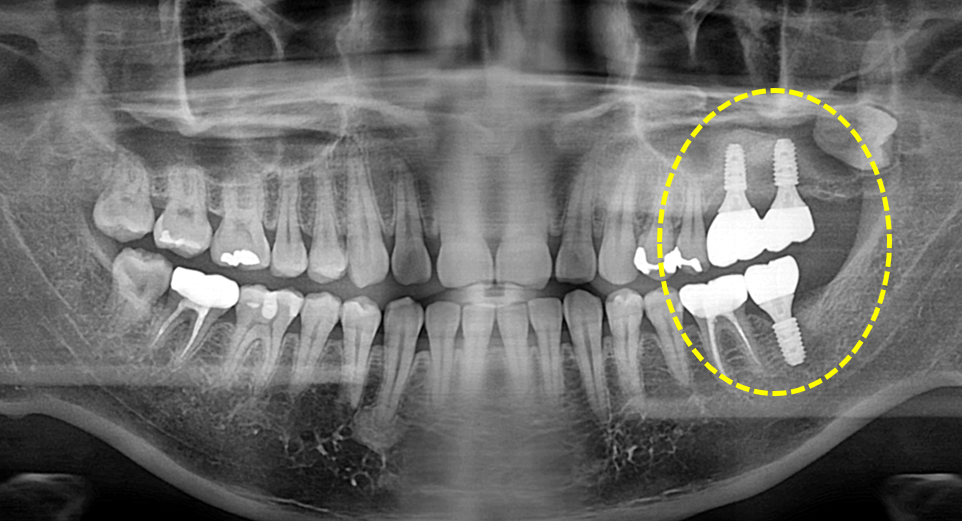

상악동 거상술을 동반한 임플란트 보철.

Before

After

치주염으로 인해 치조골이 많이 소실된 상태라고 하더라도 상악동 거상술을 동반한

치조골 이식을 통해 임플란트 뿌리 기둥을 고정하고 보철을 완료할 수 있습니다.

정확한 위치와 적절한 깊이에 임플란트를 식립함으로써

보철 후 부작용을 줄일 수 있습니다.